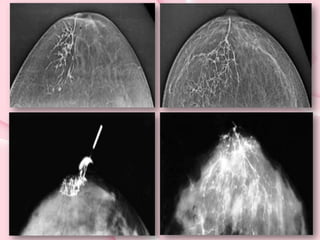

• GALACTOGRAFÍA: Es una mamografía

con contraste. El contraste se

introduce por el pezón, rellenando los

conductos galactóforos para localizar

una posible lesión Está especialmente

indicada en el estudio de la secreción

anómala del pezón o telorrea.

Galactografía

• Como resultado obtendremos radiografías

de la mama en cráneo-caudal y lateral con

los conductos galactóforos llenos de

contrate